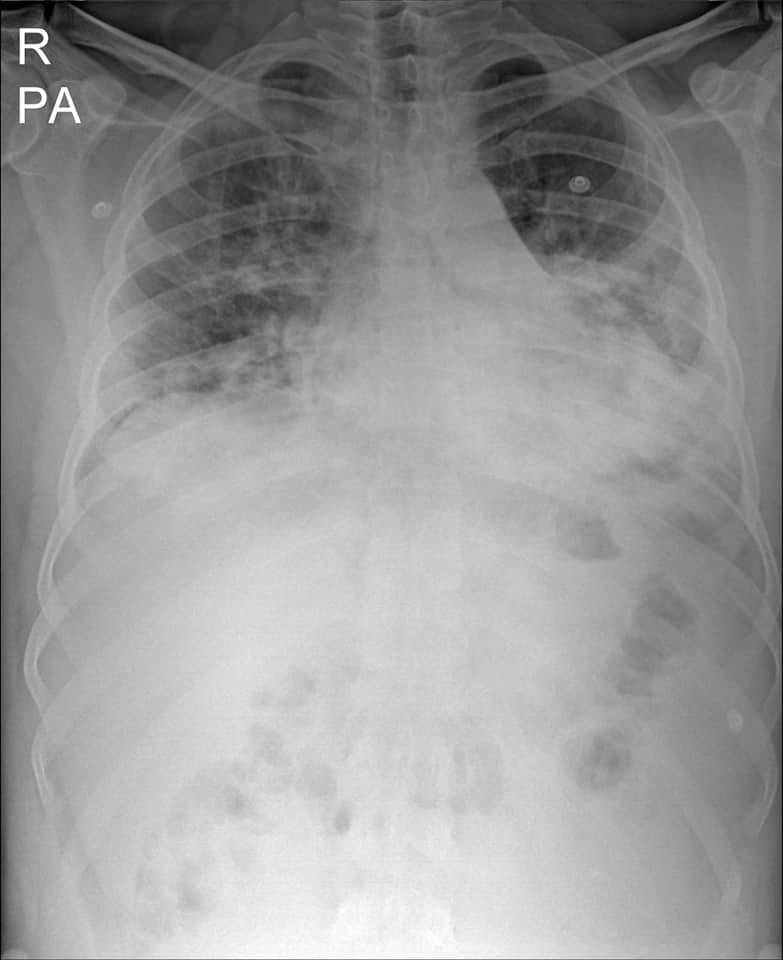

“មានបទពិសោធន៍ជាង1ឆ្នាំក្នុងគ្រប់គ្រង និងព្យាបាលជំងឺកូវីដដោយគ្មានការភ័យខ្លាចឬតក់ស្លុតឡើយ ។ តែក្នុង1ខែចុងក្រោយនេះចាប់ពី 20 កុម្ភៈ 2021 ខ្ញុំមានអារម្មណ៍ភ័យខ្លាច និងព្រួយបារម្ភណាស់ ពីព្រោះវាជាប្រភេទមេរោគប្រែរូបថ្មី (variant virus strain) ដែលក្នុងរយៈពេលតែ2ទៅ5ថ្ងៃវាវាយលុកចូលសួតធ្វើអោយរលាកធ្ងន់ធ្ងរទាំងសងខាង ។ រូបភាពសួតត្រូវបានមេរោគស៊ីសុះសាច់ដ៏គួអោយខ្លាច ។